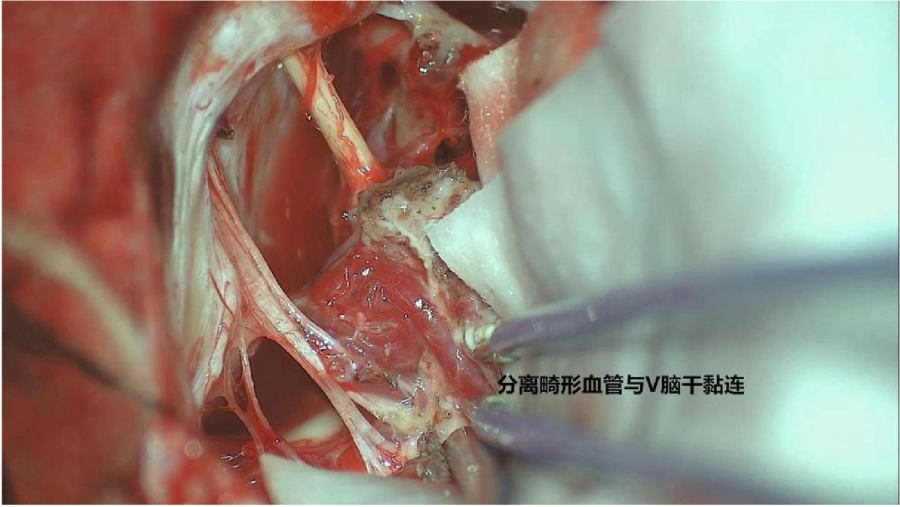

⾏左侧远外侧⼊路脑⼲⾎管畸形切除术,术中所⻅:

3、脑⼲动静脉畸形⼿术切除是注意辨别供⾎动脉与引流静脉,其往往不似其他部位的动静 脉畸形,有叫粗⼤的引流静脉。术中如果不能辨清各⾎管来源与去处,往往会造成不可估量的损失。